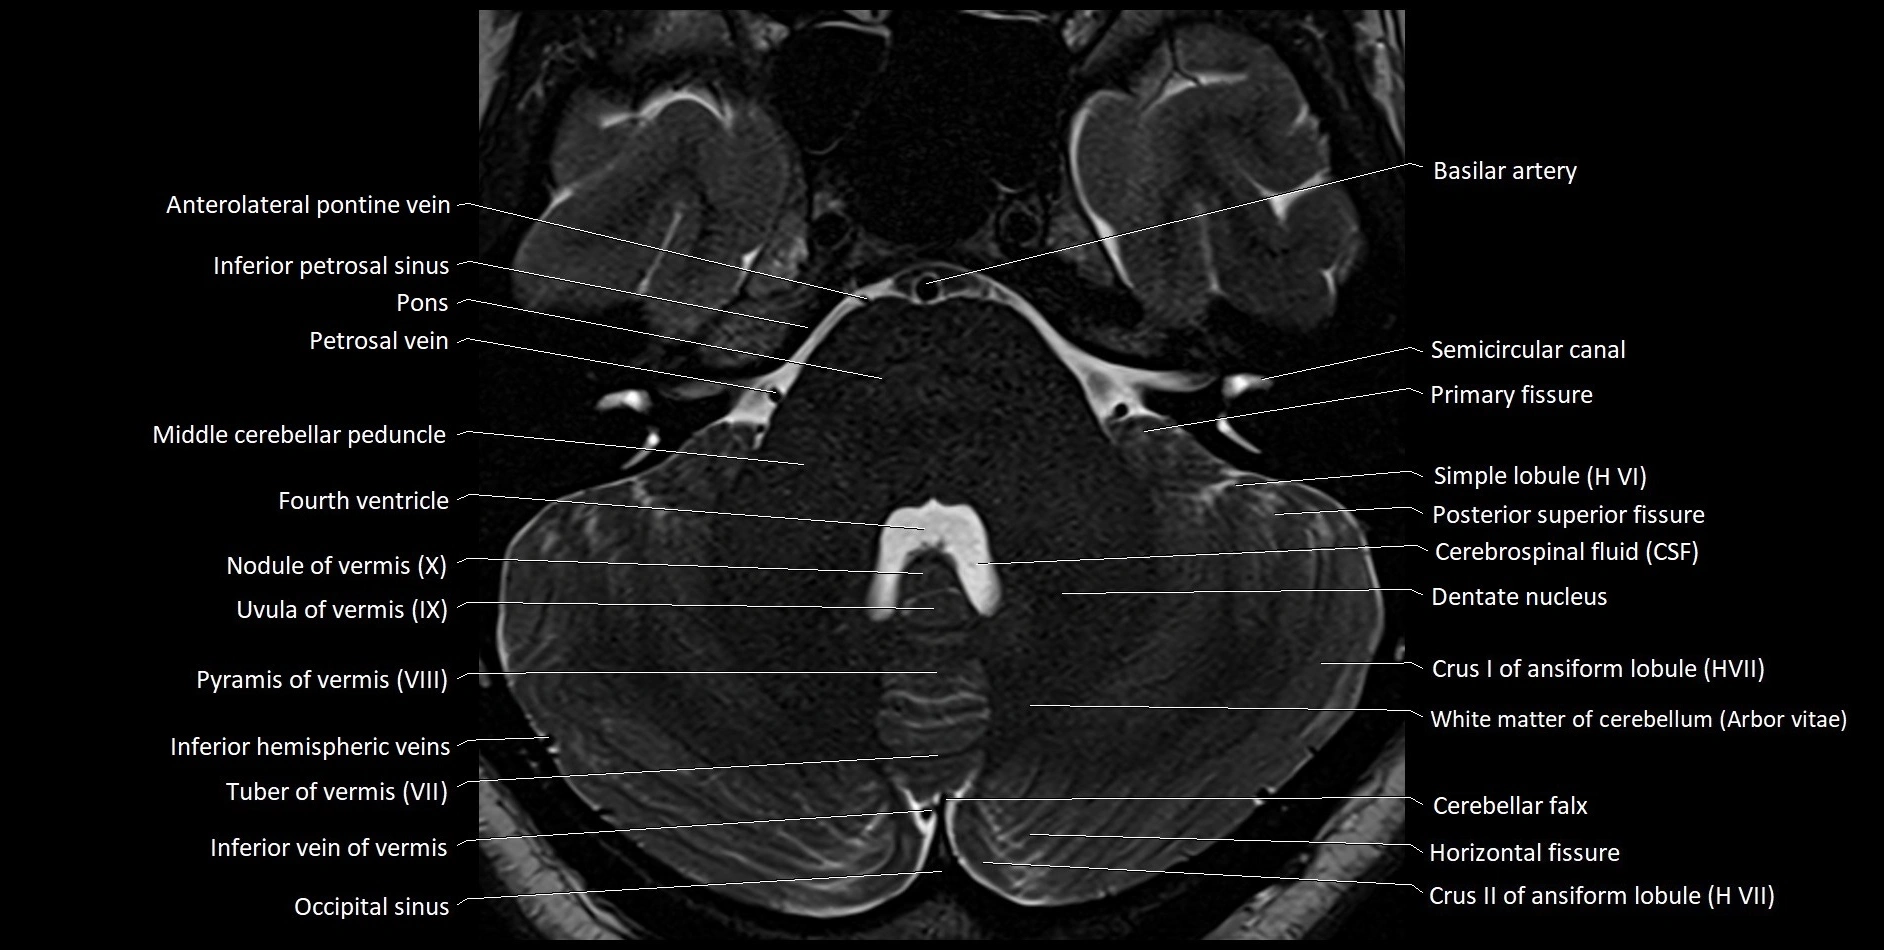

MRI images